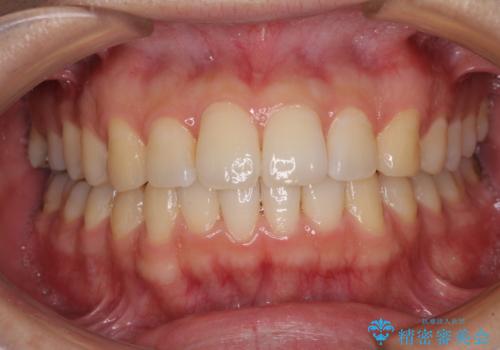

インビザライン・ライトによる矯正治療の後戻り改善

- 矯正治療の後戻りを気にして来院された患者様です。

後戻りは軽微でしたので、インビザライン・ライトにより矯正治療を行うこととしました。

再矯正後の後戻りを防ぐため、歯列排列後に、下顎前歯はワイヤーによる固定を行いました。

下顎前歯の歯列を動かないようにしておくことで、上顎前歯の後戻り防止にも効果を発揮します。